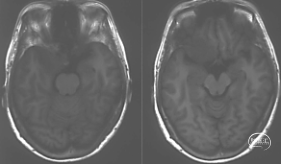

术前影像学检查

头颅MRI+增强